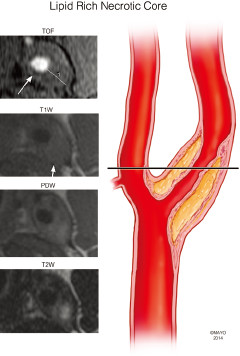

讨论:狭窄率一样,治疗方法就一样吗?

题目:四个患者ABCD去医院体检,都做了超声,发现有颈动脉斑块,且管腔狭窄率基本一样(60%左右),后续又安排做了高分辨核磁,发现A的斑块以钙化为主,B以大脂质核为主,C有斑块内出血,D的斑块已经破裂(如下图所示),ABCD都尚未出现脑缺血症状······

B

2.jpg